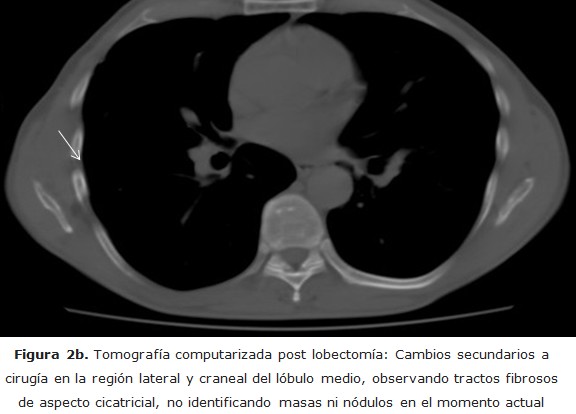

En la analítica sólo destaca una eritrosedimentación de 38 mm, proteína C reactiva en 3 mm/l y el antígeno específico prostático 0,002 ng/ml. Se indica tratamiento con amoxicilina 500 mg cada ocho horas, ambroxol un comprimido cada ocho horas e ibuprofeno 600 mg cada ocho horas durante 10 días. Al no mejorar, se realiza radiografía de tórax en la que se observa un nódulo subpleural a nivel del lóbulo medio pulmón derecho (figura 1).

figura 1